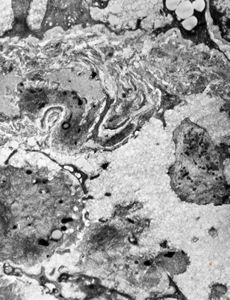

Whipple disease